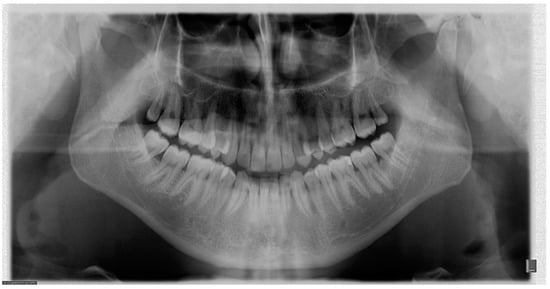

5. The Importance of Head Orientation

6.1. Symmetry

6.2. Inclination of the Occlusal Plane

6.3. Localization of Mandibular Condyles

6.4. Aspect of Upper Teeth Root Apexes

6.5. Position of the Cervical Spine